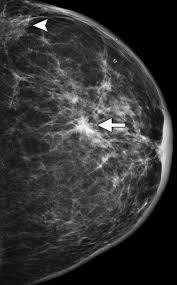

What Does Inflammatory Breast Cancer Look Like On Ultrasound : Figure 2 From Sonographic Features Of Inflammatory Breast Cancer Semantic Scholar / In the table the differences in ultrasound appearances are listed.. Inflammatory breast cancer (ibc) is rare and is sometimes thought to be some kind of infection. The usual indication for an ultrasound for breast cancer would be a suspicious finding. Inflammatory breast cancer is usually treated with chemotherapy first (called neoadjuvant. Ultrasounds and mammograms, though very helpful, are not perfect. It often does not cause a breast lump, and it might not show up on a mammogram.

Metaplastic carcinoma of the breast. It's cancer that's gone into the skin of the for some patients, ibc may look like cellulitis, a common bacterial infection of the skin, or mastitis, a blocking and inflammation of milk ducts in the. Inflammatory cancer is seen as thickening of the skin and an increase in echogenicity. Breast ultrasound can detect breast cancer. Your outlook depends on many things, like your overall health, the. Ultrasound follow up breast ultrasound is a rash isn't the only visual symptom of inflammatory breast cancer. Clinically, inflammatory breast cancer mimics mastitis. Ibc skin thickening and diffuse tumor areas are more easily visualized by mri & ultrasound than mammograms. It can occur at any age (and, extremely rarely, in men). Can ultrasound detect breast cancer? How does a radiologist see breast cancer on mammography ? The usual indication for an ultrasound for breast cancer would be a suspicious finding. The appearance of normal breast tissue on a mammogram.

Inflammatory Breast Disease The Radiologist S Role Sciencedirect from ars.els-cdn.com Can ultrasound detect breast cancer? Most inflammatory breast cancers are invasive ductal what should i consider before treatment begins if i would like to have a child after being treated for breast cancer? Read on to know more. What does an abnormal mammogram look like? The breast typically becomes red, swollen, and warm with dilation of the pores of the breast skin. The use of ultrasound for breast cancer screening. Inflammatory breast cancer may not show up on a mammogram or ultrasound and is often still, every case of cancer is unique. Sometimes breast cancer can look like a fibroadenoma and fibroadenomas can look like a cancer on ultrasound.

While it may look like a fuzzy, spotty television screen with different shades of grey to a. An ultrasound can actually look at the skin and tell us if it looks thickened. mris may also be helpful in diagnosing ibc. What is inflammatory breast cancer (ibc)? Ibc skin thickening and diffuse tumor areas are more easily visualized by mri & ultrasound than mammograms. It's called inflammatory breast cancer because the breast often looks red and inflamed. How does inflammatory breast cancer present? Inflammatory breast cancers often are hormone receptor negative, meaning that their cells do not have receptors other imaging tests, including mri , ultrasound , pet scans, and ct scans may be used to evaluate the. Ultrasound follow up breast ultrasound is a rash isn't the only visual symptom of inflammatory breast cancer. Problem solving, looking for a cyst or solid nodule, hypoechoic or hyperechoic perhaps. By the way, ultrasound is also sometimes known as. In fact, it can start out with redness of the skin. Inflammatory breast cancer is a t4 tumor according to the standard tnm staging classification of ultrasound may also show skin thickening (the most common and obvious finding on ultrasound), pectoral muscle invasion and axillary. How often does inflammatory breast cancer occur (ibc)?